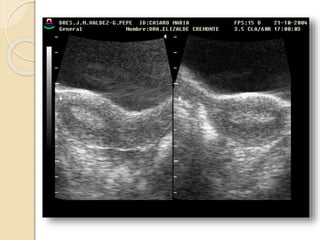

FIBROMA O LEIOMIOMA UTERINO

Patología común del útero que ocurre aproximadamente

en el 40% de las mujeres mayores de 35 años.

Los fibromas habitualmente son múltiples y más

comúnmente asintomáticos.

Se clasifican en:

• Submucosos: son los menos frecuentes pero es mas

probable que produzcan síntomas.

• Intramurales: Es el tipo mas común.

• Subserosos: Con frecuencia son pediculados y

pueden simular masas anexiales.